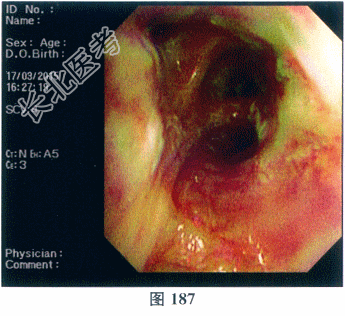

- 多项选择题3.[提示]患者纤维支气管镜检可见气管黏膜充血伴脓性分泌物,分泌物培养未发现曲霉菌及其他病原菌包括抗酸杆菌。黏膜活检病理检查: 增生的纤维组织呈慢性炎性改变,内见小灶增生的复层鳞状上皮; 抗酸染色(-)、PAS染色(-)。支气管灌洗液培养:未见曲霉菌生长, 大肠埃希菌(+),超广谱β-内酰胺酶(ESBL)阳性。免疫指标检测: ANA(+);核型1滴度1: 320,核型2滴度1: 100,抗干燥综合征抗体(SSA)阳性(+++)。胞质型ANCA(C-AN-CA)阳性。蛋白酶3型ANCA(PR3-ANCA)阳性(+++)。血清总IgE正常。纤维支气管镜检见图186、图187。目前该患者诊断为( )